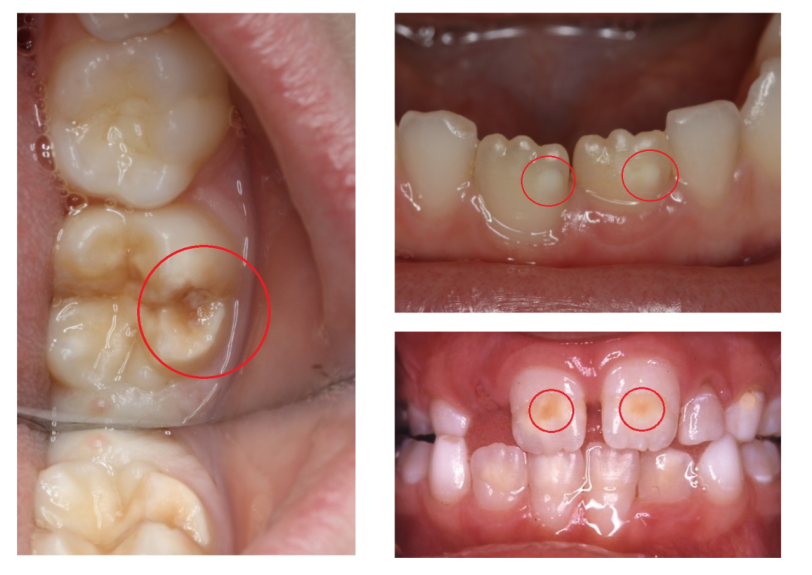

Sygdommen viser sig især på de blivende voksentænder, der hos de fleste børn begynder at titte frem omkring 6-årsalderen, og den kan kendes på, at den giver pletter på tænderne. MIH gør tænderne mere udsatte for karies, altså huller i tænderne, og kan også gøre tænderne ekstra følsomme, så det gør ondt, når barnet spiser og drikker kolde eller varme ting.

- MIH viser sig som pletter på emaljen, der kan være hvide eller cremefarvede eller mere gullige og brune. Jo mørkere pletterne er, jo værre er tilstanden. Emaljen er svag og skrøbelig i de her områder, så nogle gange falder den helt af, forklarer hun.

Sygdommen rammer de blivende voksentænder, især de kindtænder, der bryder frem ved 6-års alderen, men kan også ramme fortænder og i sjældne tilfælde hjørnetænder.